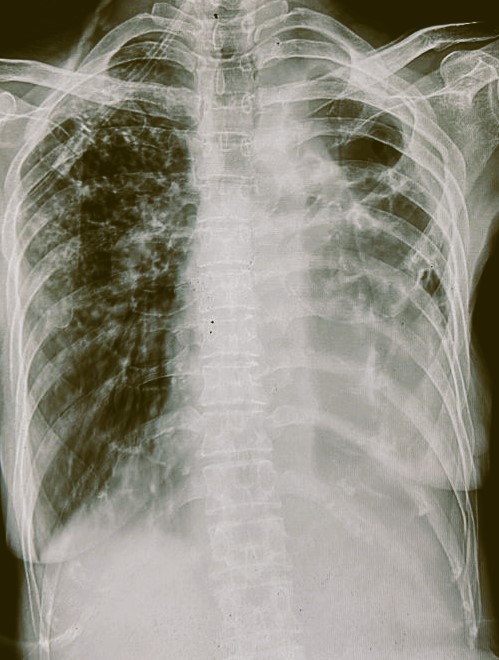

| 318 | IGGMC, Nagpur, Nagpur | P2 | 29-4154 | Tahera Bee | Consent taken on Paper | 70 Yrs. |

Provisional Diag : Post TB Bilateral Bronchiectasis

Final Diag : Post TB sequalae, Bilateral Bronchiectasis In Lower Lobe With Type 1 Respi Failure With Sepsis With Septic Shock With SYST HTN |

Post TB Sequelae | Abnormality visible on x-ray |